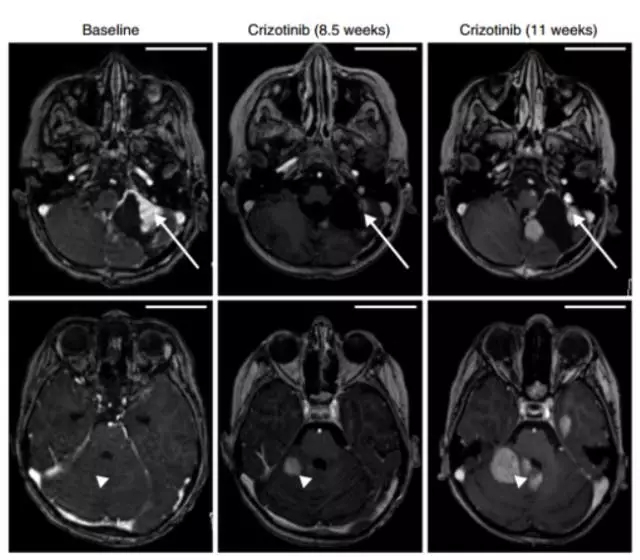

儿童胶母中较常见的致癌基因融合约占10%,MET基因融合为其中的典型,下图左为MET基因融合的类型。MET融合激活MAPK信号通路,破坏细胞周期调控,诱导肿瘤进展。MET抑制剂的模型研究发现其能抑制MET突变的肿瘤生长。

一名8岁的男孩,具有复发的小脑胶质母细胞瘤,伴随PTPRZ1-MET基因融合,使用MET抑制剂克唑替尼治疗后,11周内肿瘤显著减小(如右图上方长箭头所示),此位置症状缓解,但其他的位置发生新的耐药病灶(如右图下方三角箭头所示),由此可见综合治疗可能是达到持久临床获益的必经之路。

MET融合形式及MET抑制剂治疗效果